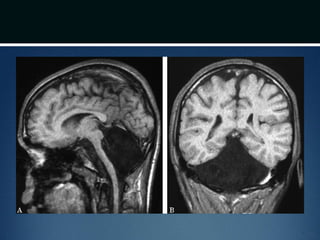

โ€ข Chiari II

โ€ข caudal migration of cerebellar vermis

โ€ข almost always occurs in patients with neural tube

defects (myelomeningocele and encephalocele)

โ€ข syrinx is common

โ€ข HCP in 90% cases

Chiari II malformation

โ€ข Caudal displacement of cerebellar vermis, lower

brainstem and fourth ventricle seen exclusively in

patients with myelomeningocele

โ€ข Numerous other anomalies associated in various

combinations

โ€“ vertical straight sinus

โ€“ large venous lakes in the tentorium

โ€“ fenestrations in falx, which is often not well formed โ€“ gyri

of left and right hemispheres interdigitate โ€“ โ€œChinese

letteringโ€ on axial MRI

Chiari II malformation โ€ขCaudal displacement of cerebellar vermis, lower brainstem and fourth ventricle seen exclusively in patients with myelomeningocele โ€ข Numerous other anomalies associated in various combinations โ€“ vertical straight sinus โ€“ large venous lakes in the tentorium โ€“ fenestrations in falx, which is often not well formed โ€“ gyri of left and right hemispheres interdigitate โ€“ โ€œChinese letteringโ€ on axial MRI